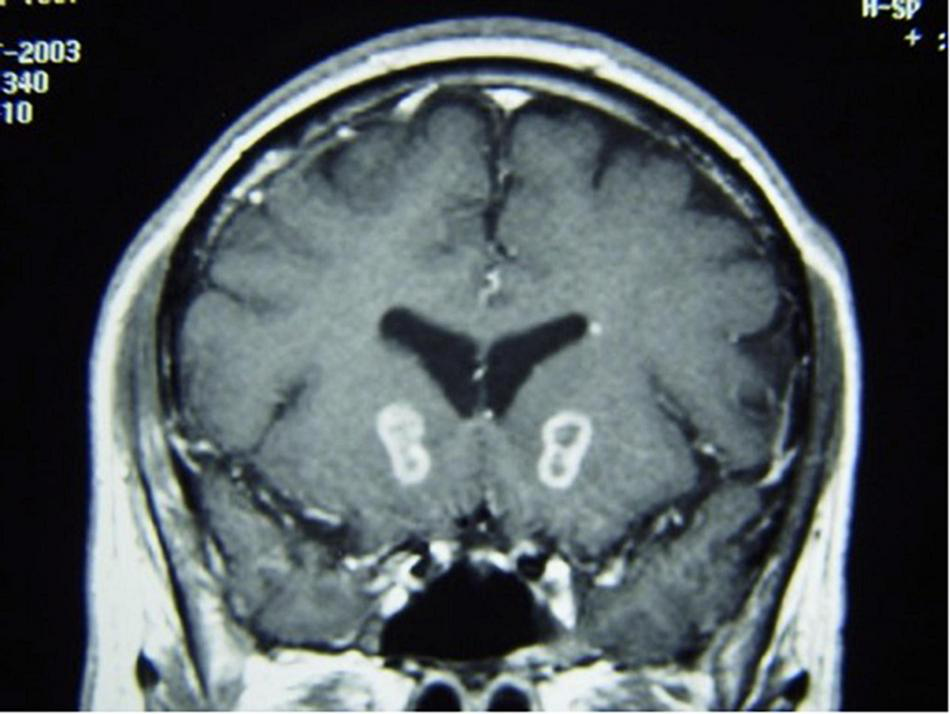

Essentially the entirety of the stereotactic radiosurgery (SRS) capsulotomy experience utilized the Gamma Knife (see Miguel et al., 2019 for a much more detailed account of the evolution of the Gamma Knife capsulotomy). Capsulotomy was initially performed with radiofrequency probes. Leksell developed the Gamma Knife as a non-invasive radiosurgical alternative to performing stereotactic capsulotomy for psychiatric illness (Leksell, 1987; Lindquist and Kihlström, 1996; Chodakiewitz et al., 2015). In Gamma Knife capsulotomy, radiation doses of 140–180 Gy, narrowed by 4 mm collimaters, are targeted to converge at an isocenter in the brain (Leksell, 1987; Lindquist and Kihlström, 1996; Chodakiewitz et al., 2015). Initial targets were chosen to treat so-called “functional disorders,” such as intractable pain, trigeminal neuralgia, parkinsonism, epilepsy, and psychoneurosis, including severe anxiety and OCD (Leksell, 1987). Between 1968 and 1986, 1,311 capsulotomy procedures were performed at the Karolinska Institute (Leksell, 1987). The initial experience of Gamma Knife capsulotomy in OCD patients from the Karolinska Institute suggested that radiosurgical capsulotomy is as effective as thermocapsulotomy (Lippitz et al., 1999). Criteria of good postoperative outcome were met by 9 of 19 patients who underwent bilateral thermocapsulotomy for OCD and by 7 of 10 patients who underwent radiosurgical capsulotomy for OCD (Lippitz et al., 1999). T2-weighted MRI of stereotactic lesions in the internal capsule can accurately assess lesion location (Mindus et al., 1986). Lesions in specific areas of the right internal capsule after radiosurgery for OCD correlate with symptom improvement (Lippitz et al., 1997; Figure 8).

FIGURE 8

Coronal T1-weighted MRI with contrast of gamma knife capsulotomy lesions.